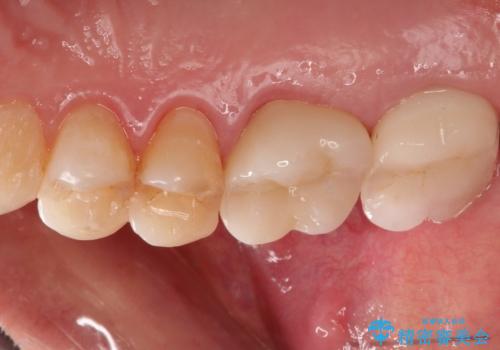

感染した奥歯 痛くて咬めない 根管治療→かぶせ物で痛みを取り除き、かみ合わせを回復する

すでに感染が根の先端まで及んでいたため、かなり強い痛みがありましたが、丁寧に根管治療をすることで内部を可及的に無菌化し、痛みが消失しました。

かぶせ物の種類:Bellezza